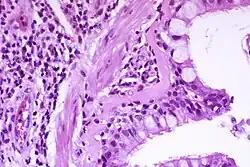

Patofizjologia

Astma jest rezultatem przewlekłego zapalenia dróg oddechowych, którego efektem jest zwiększona kurczliwość mięśni gładkich dróg oddechowych[16]. Wraz z innymi czynnikami prowadzi to do zwężenia dróg oddechowych, którego objawem jest świszczący oddech[16]. Zwężenie zazwyczaj mija niezależnie od tego, czy jest leczone, czy też nie[16]. Czasami może dochodzić do histologicznej przebudowy tkanek dróg oddechowych[16]. Najczęściej spotykane zmiany dróg oddechowych obejmują zwiększenie ilości eozynofili oraz pogrubienie blaszki siateczkowatej[15]. Po pewnym czasie mięśnie gładkie dróg oddechowych mogą zwiększyć swój rozmiar; może się także zwiększyć liczba gruczołów śluzowych[15]. Inne rodzaje uczestniczących w tym procesie komórek to limfocyty T, makrofagi oraz neutrofile[15]. Może również dochodzić do zaangażowania innych części układu immunologicznego, włączając w to m.in.: cytokiny, chemokiny, histaminę oraz leukotrieny[15].